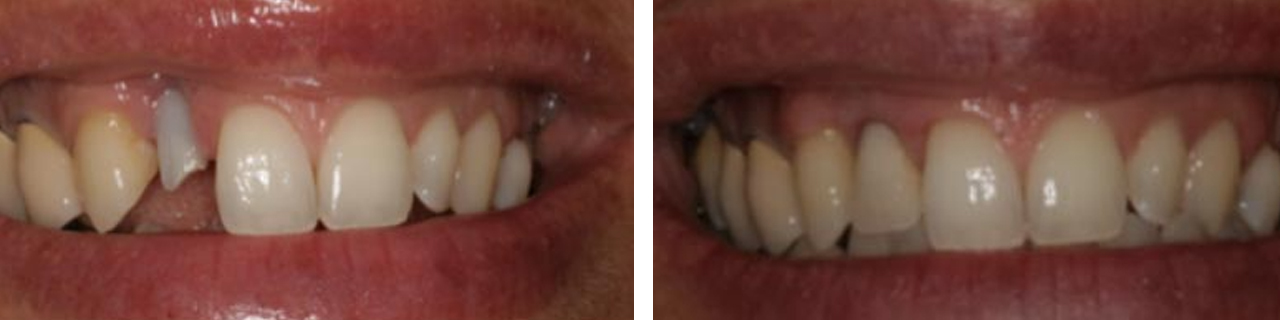

Regeneración de hueso y encía previo al implante.

Cubrimiento gingival de implante